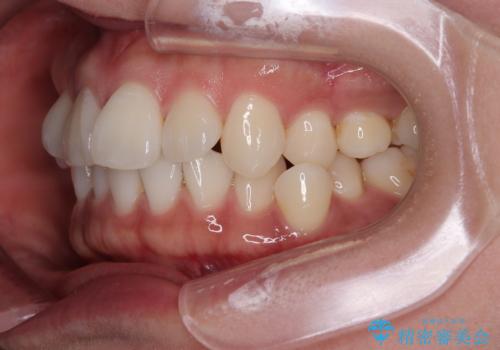

初診時、上下顎ともに歯列の不正が認められ、特に左下の小臼歯が大きく歯列から外れている状態でした。その影響により、下顎の正中が左側へシフトしており、見た目だけでなく噛み合わせにも影響が出ていました。

- 「歯並び全体のデコボコが気になる」「上下の歯の正中(中心)がずれているのが気になる」

このようなお悩みを主訴にご来院された患者様の矯正治療症例をご紹介します。